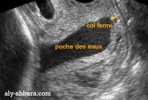

Et ici une écho préoccupante (pas la mienne) où on voit que la majeure partie du canal est occupée par la poche des eaux, en noir (mon cas aussi, mais pas autant... pour le moment) avec une portion fermée très réduite (le canal encore fermé est tracé en orange) :

1663307787354.png